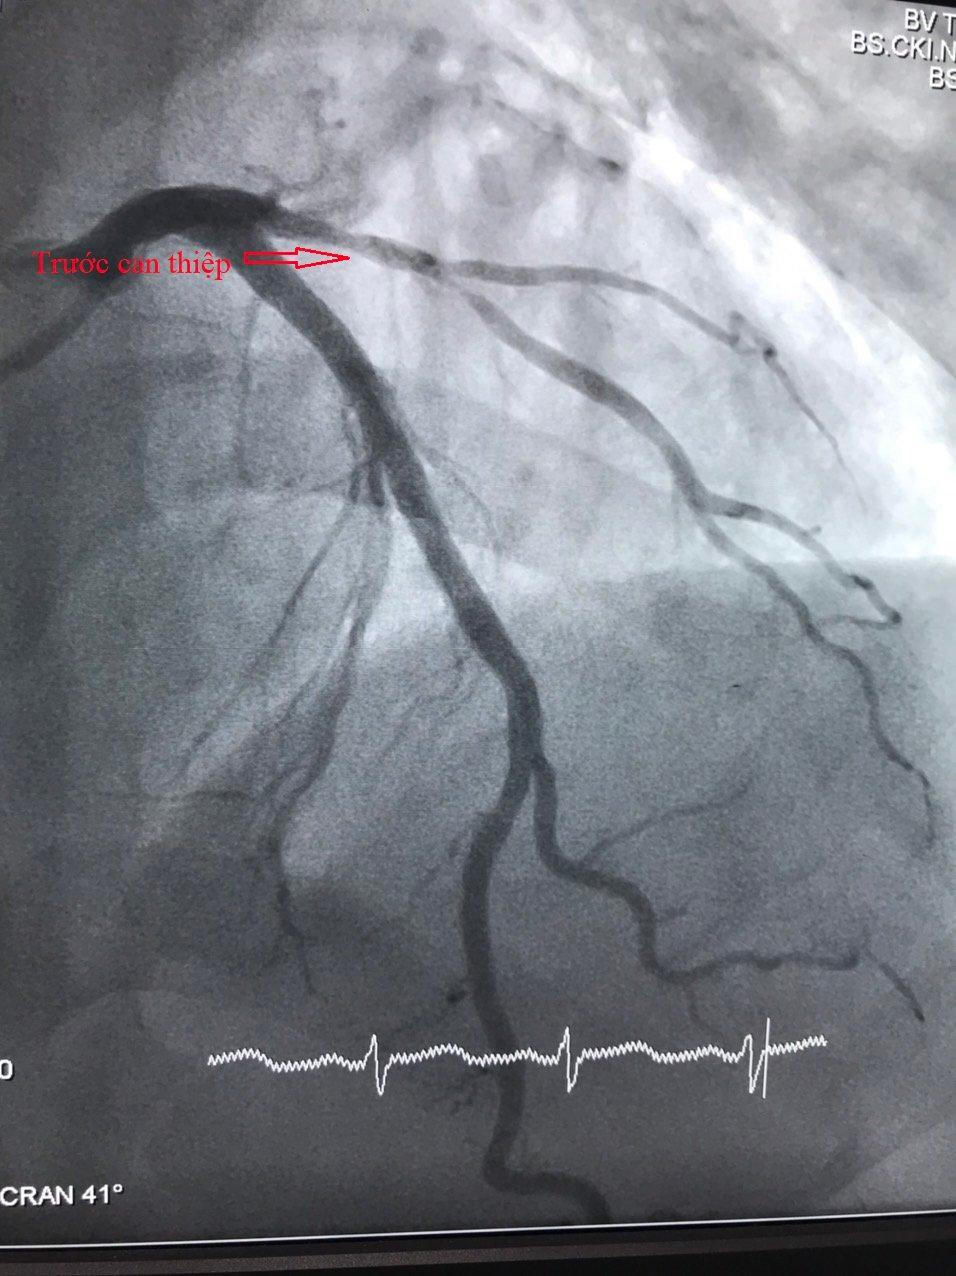

Kết quả chụp mạch vành ghi nhận động mạch liên thất trước (LAD) bị thâm nhiễm, hẹp 80%-90% nhánh chéo 1, các bác sĩ tiến hành can thiệp mạch vành cho bệnh nhân bằng cách nong bóng và đặt stent phủ thuốc với thời gian 30 phút.

Hình ảnh tổn thương mạch vành trước can thiệp |